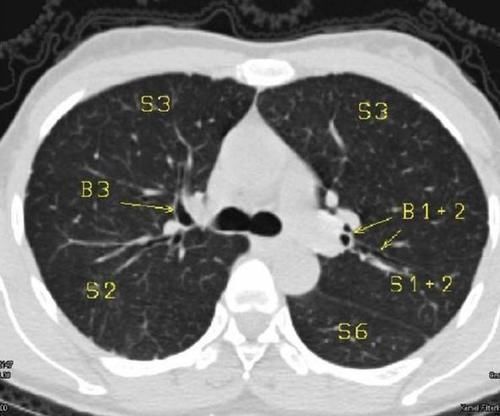

准确的说肺结节其实是影像科医师对于胸部CT显示的局灶性病灶的一种描述。我们通常把胸部CT上直径小于3cm肺部病灶统称为肺结节。